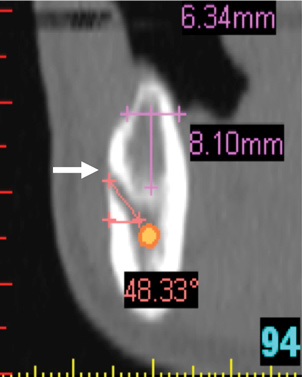

Fig 8. Deficient ridge contour at the osseous crest: cross-sectional view. This ridge (arrow) is not wide enough to receive an implant unless additional bone grafting is done to accommodate the implant’s width or the bone is reduced to a widened part of the ridge suitable for implant insertion.

Figure 8